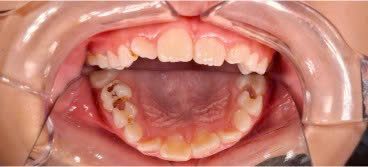

Duy trì được răng sữa đến đúng thời điểm thay răng, ngăn ngừa mất khoảng và sai lệch cung răng.

- Giúp răng giữ chức năng nhai, phát âm và thẩm mỹ trong giai đoạn phát triển.